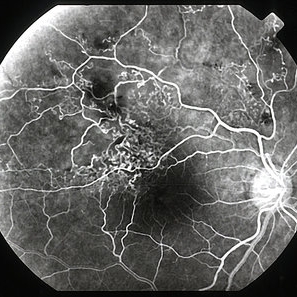

CRVO post LICRA - FA 1

Jan 11 2013 by Alex P. Hunyor, MD

Extensive NVD, NVE and vitreous haemorrhage complicating previous attempted laser-induced chorioretinal anastomosis for CRVO, left eye - early fluorescein angiogram. Note: this is a scanned film negative FA. Note also subretinal neovascularisation at superotemporal anastomosis site.

Condition/keywords: central retinal vein occlusion (CRVO), laser treatment